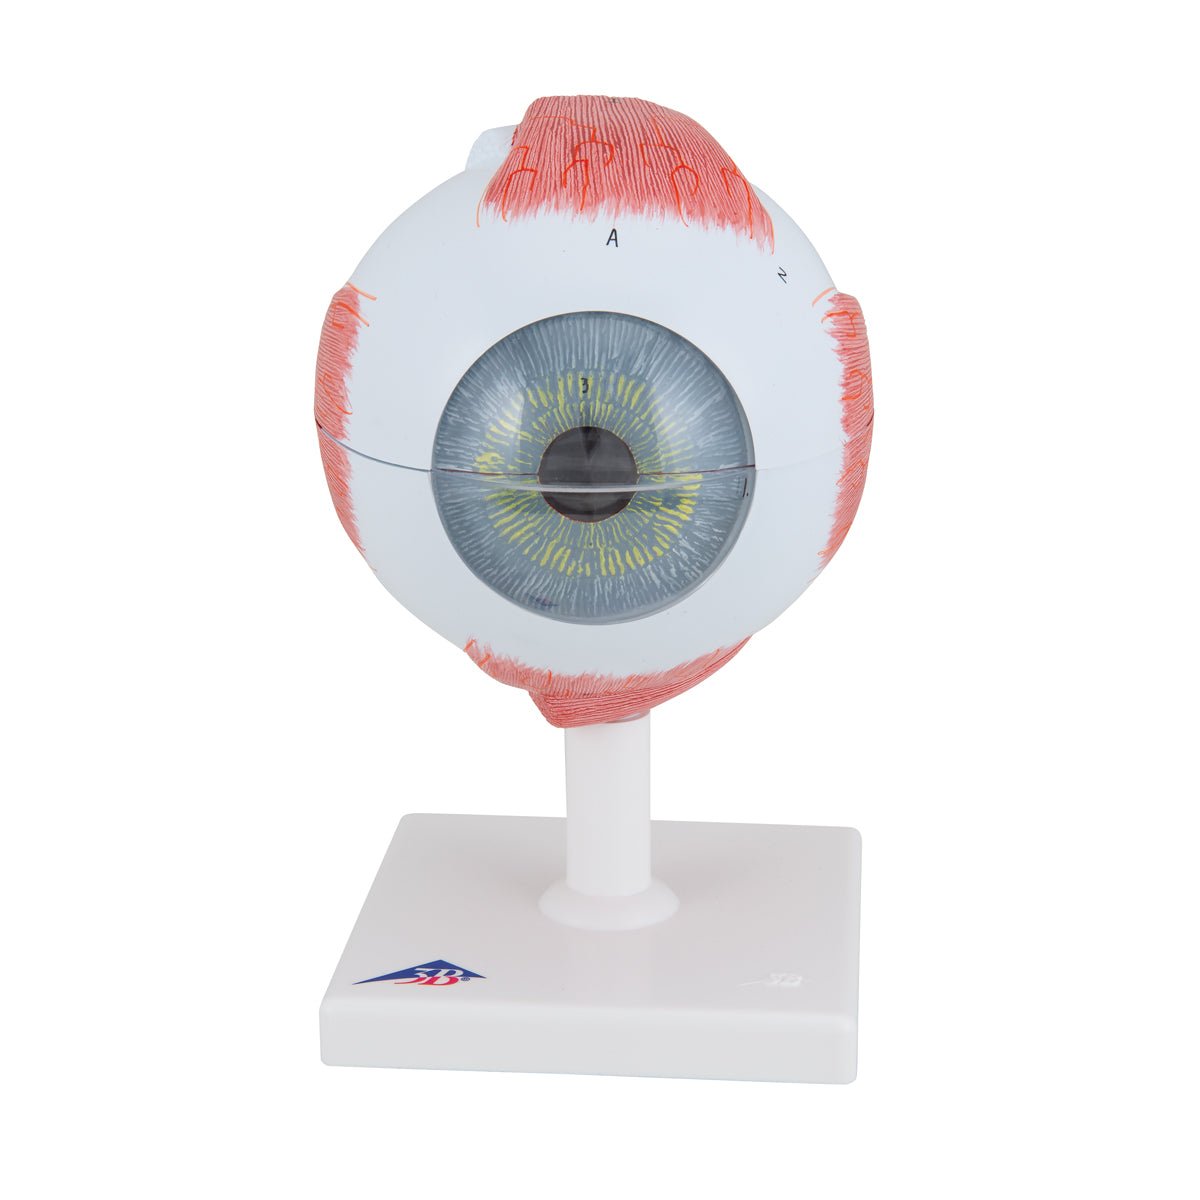

Anatomical models

Selling anatomical models is the mainstay of eAnatomi, although we also spend a lot of resources developing our own anatomical materials such as posters. Anatomical models are used for various purposes and can show both defined tissues, organs and organ systems. Are you looking for a simple model of bone tissue or perhaps an advanced torso model based on MRI technology, you can find it all at eanatomi.com.